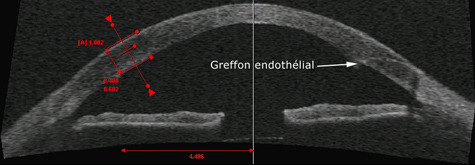

D - Les greffes endothéliales

Quand la couche de cellules endothéliales est atteinte de manière isolée, il est possible depuis 2005 de ne changer que cette partie de la cornée.

Cette technique préserve l’anatomie cornéenne. En effet, il n’y a pas de trépanation. Seule, une petite incision de 4 mm est nécessaire sur la partie périphérique de la cornée.

L’endothélium du receveur (couche de 50 microns d’épaisseur) est retiré à travers l’incision.

Sur le greffon, l’endothélium est prélevé avec un peu de stroma. La technique de prélèvement la plus utilisée est mécanisée. Le prélèvement est difficile. L’intervention peut même être annulée par impossibilité de prélèvement. L’intervention est dans ce cas repoussée de quelques jours ou semaines, dans l’attente d’un nouveau greffon.

L’endothélium du donneur est introduit dans l’œil du receveur. Il est fixé à la face interne de la cornée grâce à la pression d’une bulle d’air. Pendant les 24 heures qui suive l’intervention, il est important de se positionner avec la face vers le plafond, afin que l’air puisse faire son effet.

Il n’y a aucune suture dans le greffon.